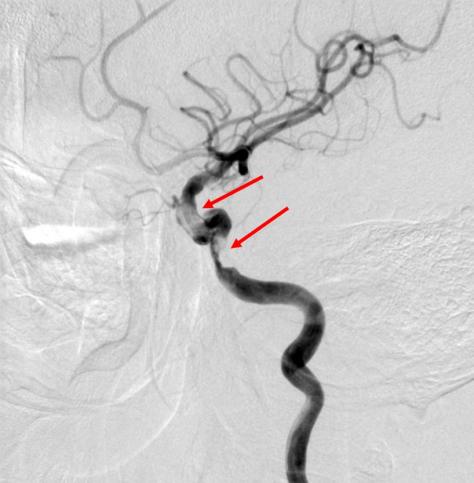

老冯(化名)因近半年间断发作视物模糊、伴间断肢体力弱,来到北大医院神经内科就诊。在门诊做了核磁检查后发现,有新近腔梗和陈旧梗死伴出血的可能,溶栓多模态CTA则提示头颈动脉粥样硬化,不除外血栓形成。为了进一步检查,老冯办理了住院,进行了脑血管造影,检查结果发现左侧颈内动脉存在充盈缺损,高度怀疑为血栓性病变。

脑血管造影,箭头所示为狭窄部位,考虑与血栓相关